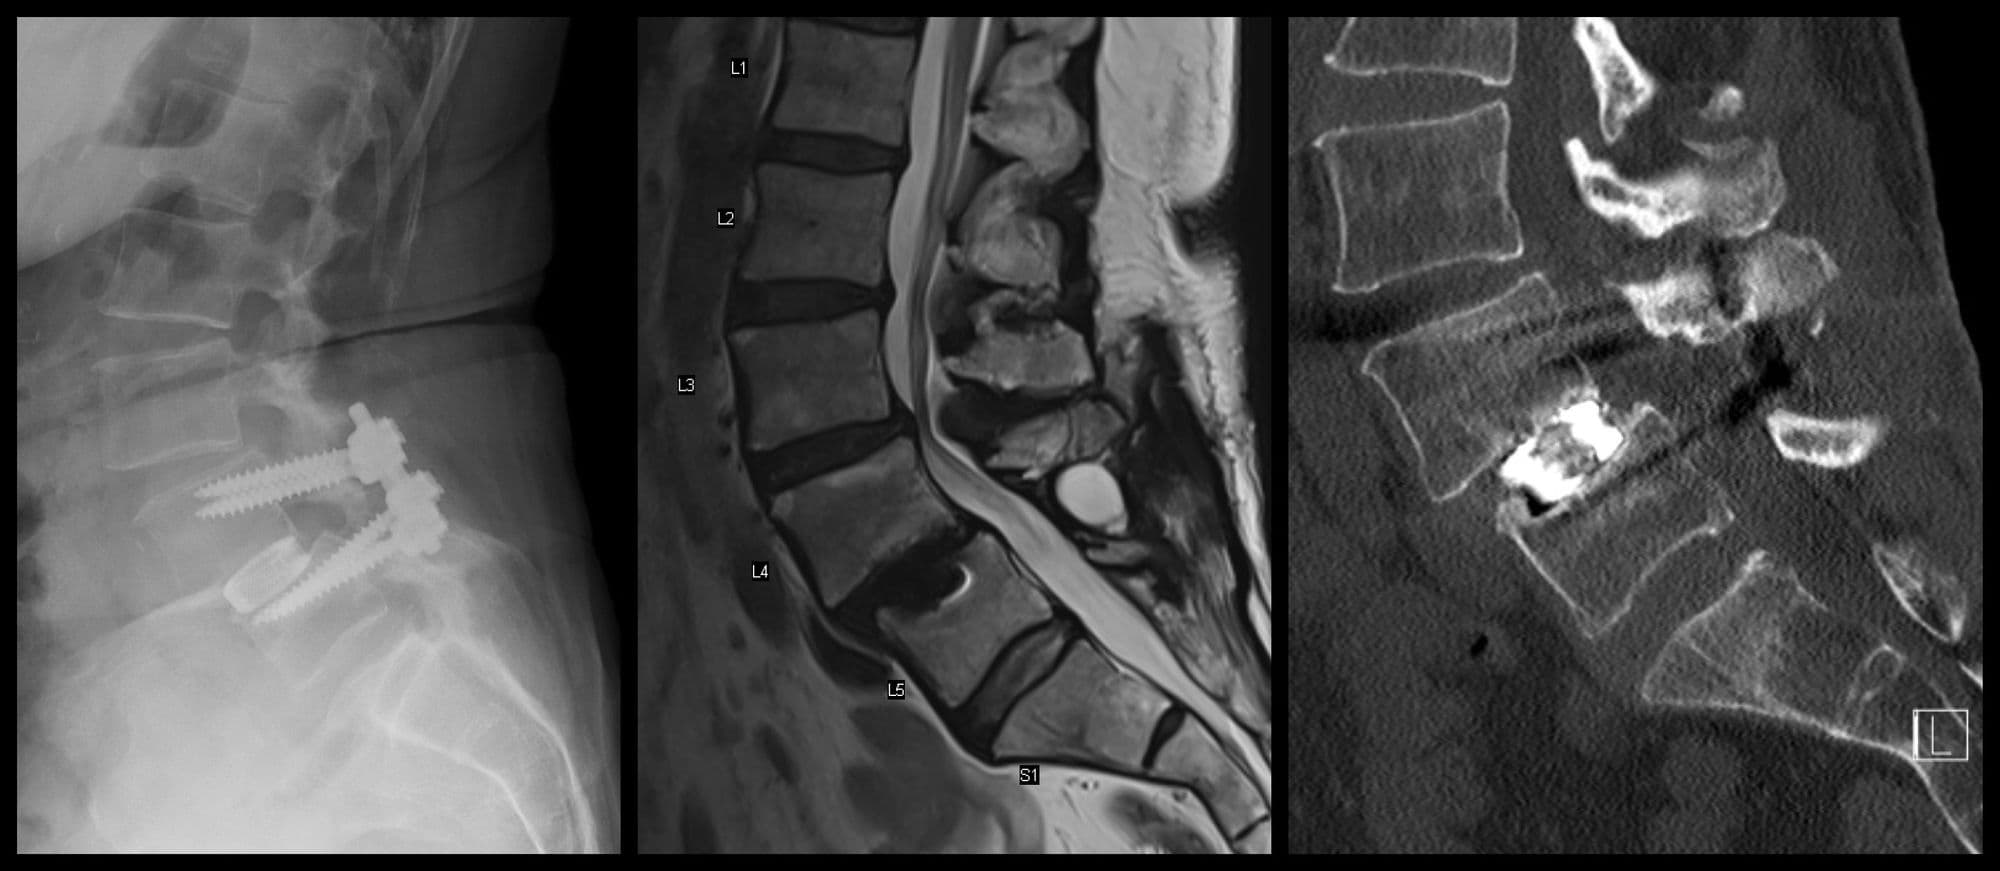

Post-op

L3-4 TLIF

Darrel Brodke